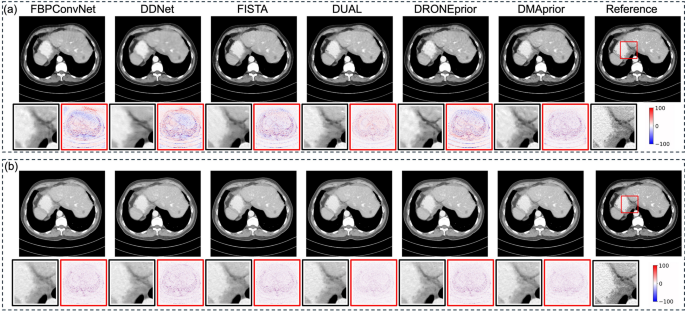

Ablation study on the effect of the dual-domain deep prior image-guided iterative reconstruction framework on AAPM simulated dataset with 64 views. (a) Comparison of different prior images generated by FBPConvNet, DDNet, FISTA, DUAL, DRONE prior, and our DMA prior. (b) Reconstruction results after iterative optimization with different prior images. The bottom row of each subfigure shows the zoomed ROI and error maps (difference between reconstruction and reference, color scale in HU). All images are presented with a display window of [−160, 240] HU.

The effectiveness of our DPMA framework primarily depends on the quality of the initial prior image. To address this fundamental challenge, we developed the DMA framework, which demonstrates improved performance in generating high-fidelity prior images with enhanced structural preservation. As shown in Figure 8(a), our approach achieves better alignment with reference images compared to existing methodologies, including post-processing networks (FBPConvNet, DDNet14), iterative unfolding approaches (FISTA, DUAL), and partial implementation of deep residual frameworks (DRONE prior, which comprises only the Embedding and Refinement modules from the original DRONE architecture, without the Awareness module). The quantitative and qualitative improvements observed validate our hypothesis that dual-domain integration with physics-informed constraints provides more reliable anatomical priors for subsequent iterative refinement.

Our framework allows for the integration of various models as initial priors for iterative refinement. Figure 8(b) illustrates that the iterative optimization process enhances reconstruction quality across all models, improving the delineation of anatomical structures, organ boundaries, soft tissues, and bones. The results demonstrate the effectiveness of our prior image-guided iterative strategy. Furthermore, the reconstruction quality can be further improved when starting with higher quality initial priors, such as those generated by our DMA framework. Table 2 presents the quantitative comparison between DRONE prior and DMA prior. The results indicate that our DMA prior achieves improved performance across all metrics, validating the effectiveness of the proposed dual-domain approach and MFA attention mechanism in feature extraction and reconstruction.